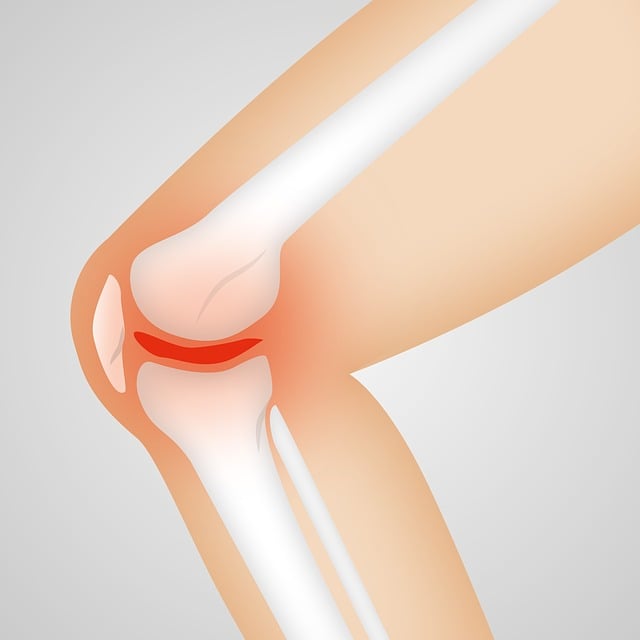

1. 퇴행성 관절염

노화에 따라 관절 연골이 닳고 뼈끼리 마찰되면서 염증과 통증이 생긴다. 특히 무릎, 고관절, 손가락 등 사용이 많은 부위에서 흔하다.